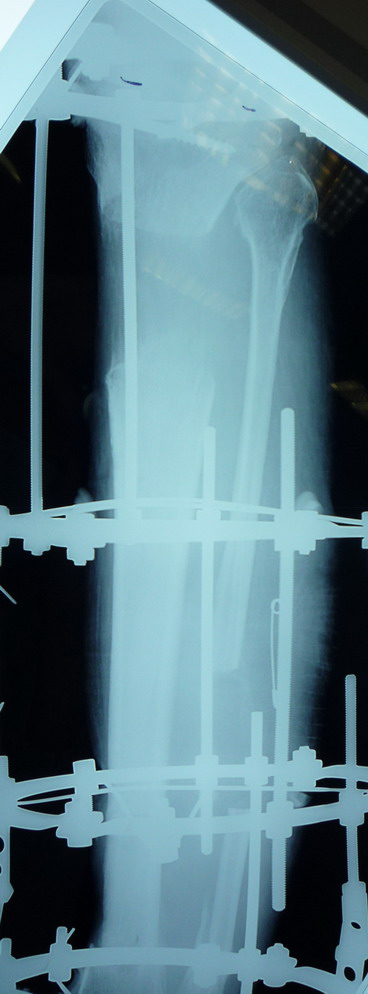

Пациент В. 53 лет, травма в феврале 2009. ДЗ. Открытый оскольчатый перелом нижней трети голени. При боли поступлении выполено ПХО, аппарат Илизарова. В последующем проводили ВХО, резекция костных отломков, укорочение 6 см, рана зажила. Была выполнена остеотомия большеберцовой кости в проксимальном отделе, резекция. Производилось тракция.

На последних рентгенограммах выявлено, что одновременно с "выращиванием" регенерата произошло низведение надколенника  на длину выращенного регенерата.

Клинически: активное разгибание сохранено, объем движений в колене 180-110 градусов.  Черными стрелками обозначен верхний край надколенника с одной и с другой стороны. Красная стрелка обозначает пальпируемую связку надколенника.

Причина - остеотомия выше места прикрепления связки надколенника.